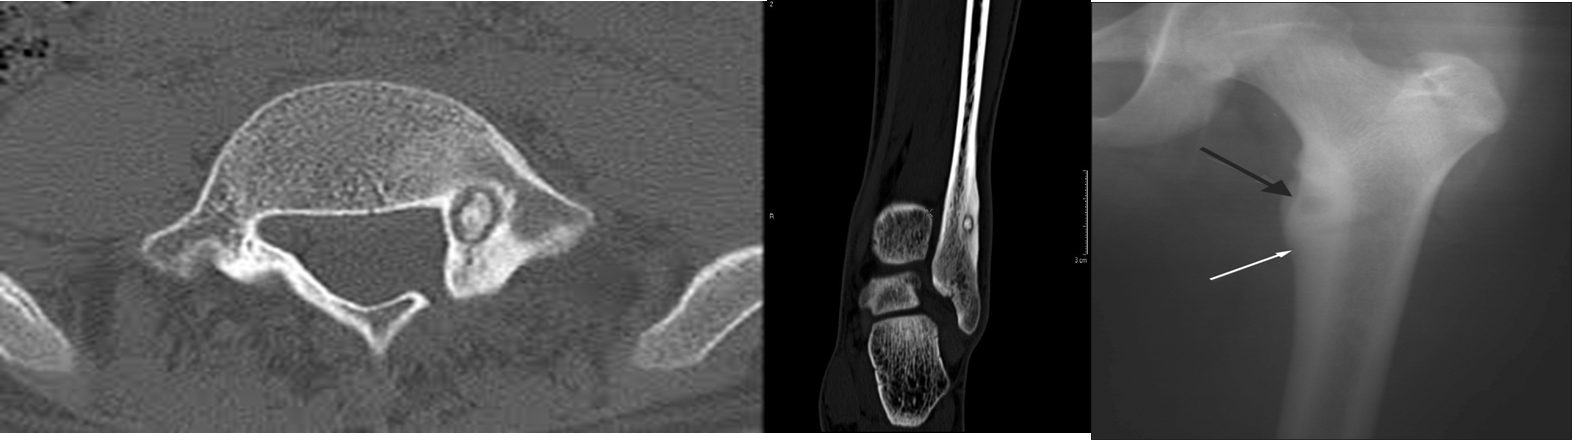

An osteoid osteoma is most common in the femur and tibia in young adults.

characteristic radiological appearance:

- a small lucency, sometimes with central specks of calcification, known as a ‘nidus’, surrounded by a dense sclerotic rim. and classically cause night-pain that is relieved by Aspirin.